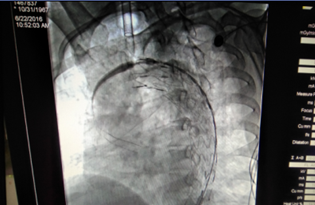

术中(释放支架)

术后(见主动脉血流规则,治疗效果良好)